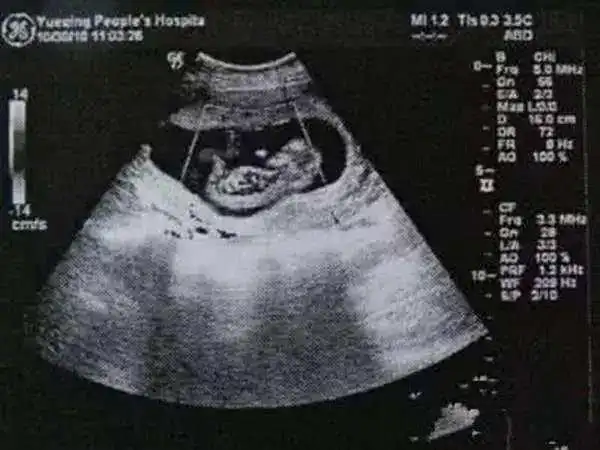

生男生女提前知道胎儿性别看这两处可以看出来